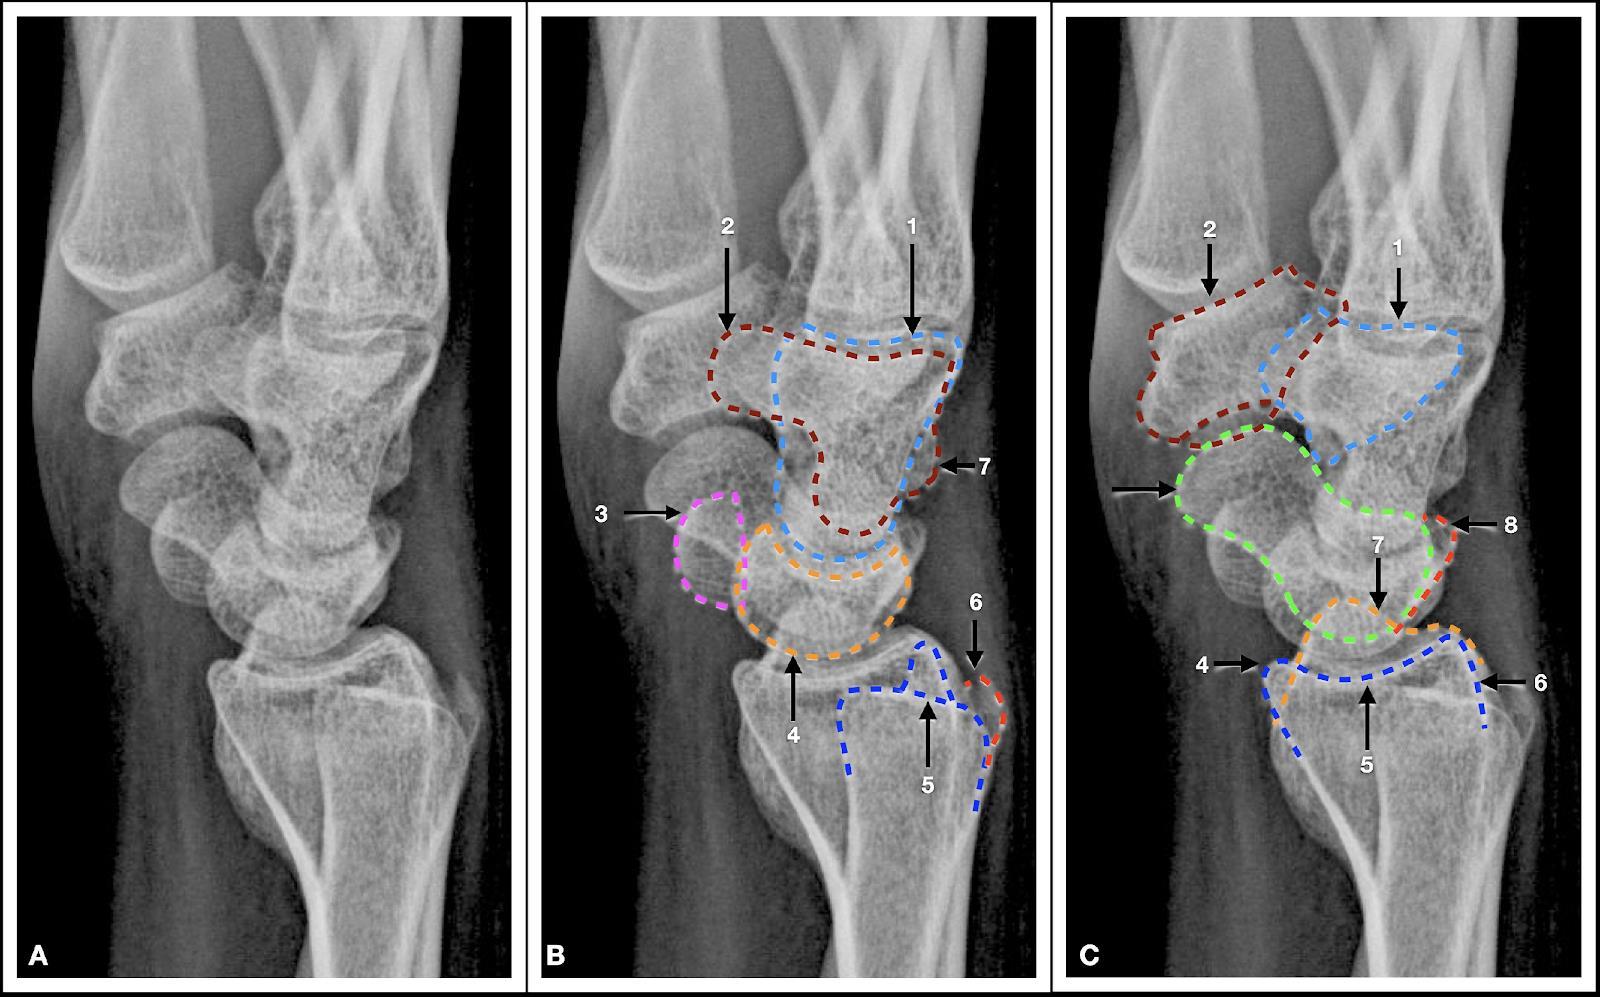

15. Anatomía radiológica del carpo

Marcela Pérez Muñoz, Camilo González Gómez…………….…………………………..